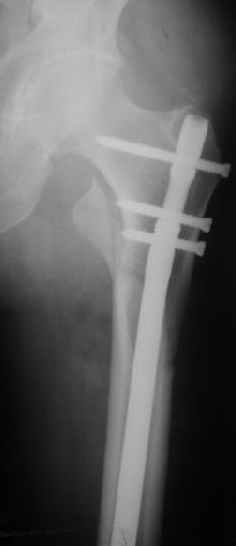

При межвертельных переломах с цефаломедуллярными гвоздями бывает, что проксимальый винт проходит или черед периферический отломок, или прямо над ним. И если остался диастаз, то этот винт при осевой нагрузке не дает сблизиться отломкам. Пример такого остеосинтеза в застарелом случае в приложении.

В качестве предупреждающей меры можно долотом разрушить латеральную стенку дистального отломка под винтом.

В частности, на проксимальном конце сделано еще одно дополнительное статическое отверстие. Можно ввести в проксимальном отделе 4 винта, из них 3 статические (2 в круглые отверстия и 1 по нижнему краю овального). Картинки в приложении. На дистальном конце стержня тоже кое-что улучшено. Спрашивайте в аптеках, как говорится. Выпускается предприятием "ЦИТО" (Москва), то есть это малобюджетное решение.

Конечно, мы не синтезируем остеопорозые вертельные переломы согласно прилагаемому примеру, винты 6 мм вырежутся. Но у более молодых при хорошем качестве кости такие или подобные гвозди с поперечным расположением винтов вполне применимы для меж- и подвертельных переломов.